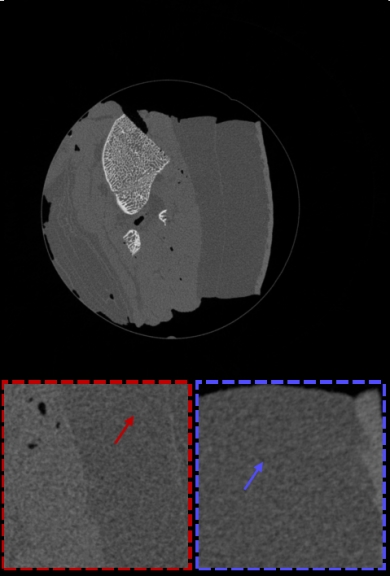

Fig. 3 and Fig. 4 show the reconstruction results of the two samples, including the uncorrected image for comparison (Fig. 3(a) and Fig. 4(a)), the corrected result of the WF method (Fig. 3(b) and Fig. 4(b)), the Podgorsak method (Fig. 3(c) and Fig. 4(c)), the Wu method (Fig. 3(d) and Fig. 4(d)), the Salehjahromi method (Fig. 3(e) and Fig. 4(e)), and the proposed method (Fig. 3(f) and Fig. 4(f)). Magnified images of regions of interest (ROIs) are shown at the bottom of each image. The locations of the ROIs are labeled with blue and red rectangles in Fig. 3(a) and Fig. 4(a), respectively.

Fig. 3 shows the reconstructed CT images of the water-and-bone sample after ring artifact correction. As can be seen from Fig. 3(a), there are severe ring artifacts on the reconstructed CT image, which significantly interfere with the interpretation of the image. The WF method successfully removes most of the ring artifacts, but it introduces new low-frequency artifacts (as indicated by the yellow arrow in Fig. 3(b)). Both the Podgorsak method and the Wu method generally correct the majority of ring artifacts while preserving image detail, however, they fall short in addressing wider ring artifacts (as indicated by the red arrows in Fig. 3(c) and Fig. 3(d)). The Salehjahromi method effectively corrects the wider ring artifacts, yet some residual artifacts remain. Furthermore, these methods struggle with handling ring artifacts that traverse different positions of the scanning sample, which results in even more pronounced ring artifacts at these locations (as indicated by the blue arrows). This phenomenon primarily stems from their lack of consideration for the correlation between the response inconsistency of detector units and the projection views. In contrast, the proposed method performs superior in removing nearly all ring artifacts, particularly excelling in the correction of wider ring artifacts and those traversing different positions of the sample.

In this paper, we propose a novel dual-domain regularization ring artifact removal model, which is characterized by considering the correlation between the response inconsistency of detector units and the projection views, and thus can better correct the ring artifacts, especially the vertical stripe artifacts whose intensity varies greatly in the direction of the projection view. The blue arrows in the ROIs shown in Fig. 3 and Fig. 4 highlight the shortcomings of several comparative methods in addressing ring artifacts that traverse different positions of the scanning sample. As can be seen from Fig. 5 that these ring artifacts correspond to the vertical stripe artifacts marked by the yellow arrows in the sinogram, which are characterized by sharp variations along the projection view direction. Since the response inconsistency of the detector unit is related to various factors including the scanning sample and the energy spectrum. Consequently, the response of the same detector unit to X-rays is different when the X-rays pass through different positions of the scanning sample at different projection views. Several comparative methods overlook the correlation between the response inconsistency of the detector units and the projection views, rendering them less effective in correcting such artifacts. Unlike these methods, the proposed method can achieve superior artifact mitigation by considering this correlation.

In some cases, the ring artifacts may be caused by the inconsistency of one whole module. That is to say, the form of ring artifacts is a wide circle, which is challenging to remove completely. The proposed method can still work in these cases. As indicated by the red arrows in the ROIs in Fig. 3 and Fig. 4, while the WF method can mitigate such ring artifacts, it unfortunately introduces new artifacts that compromise the integrity of image details. The Podgorsak method and the Wu method struggle to remove the particularly wider ring artifacts, likely due to their reliance on filtering methods that inadvertently retain such artifacts as legitimate structural components of the image. It can be seen that both the Salehjahrom method and the proposed method successfully eliminate these wider ring artifacts. We attribute this improvement to the synergistic application of the constraints in both the projection and image domains. Recognizing and rectifying such wide ring artifacts is challenging when constrained to the projection domain alone; however, employing the prior information from the reconstructed CT image allows for further correction in the image domain. Therefore, the dual-domain method facilitates a more comprehensive and effective removal of such artifacts.